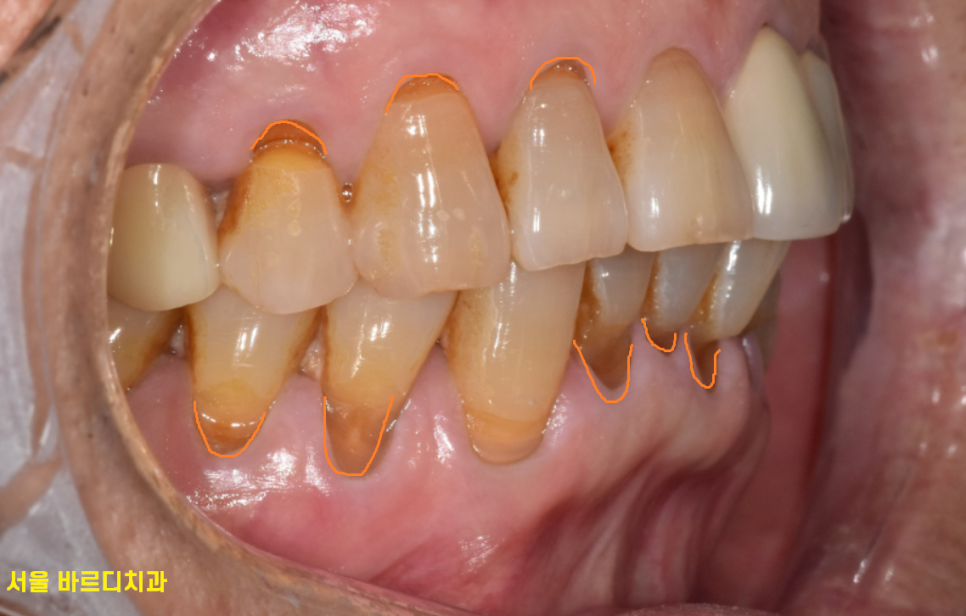

환자분은 1차 육안 소견으로

잇몸 뿌리 부분이 패인 것을 발견했지만

이것이 주요한 원인은 아닐꺼라 판단했습니다.

눈으로 보이는 치석도 많고

잇몸도 내려가서 잇몸이 안좋을 것이라 판단되었기 때문이죠.